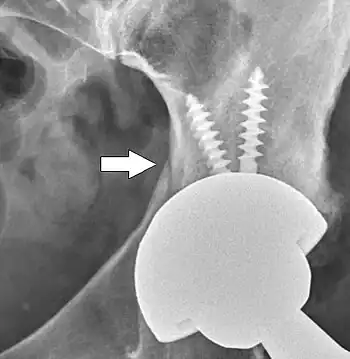

The acetabular cup is the component which is placed into the acetabulum (hip socket). Cartilage and bone are removed from the acetabulum and the acetabular cup is attached using friction or cement. Some acetabular cups are one piece, while others are modular. One-piece (monobloc) shells are either ultra-high-molecular-weight polyethylene or metal, they have their articular surface machined on the inside surface of the cup and do not rely on a locking mechanism to hold a liner in place. A monobloc polyethylene cup is cemented in place while a metal cup is held in place by a metal coating on the outside of the cup. Modular cups consist of two pieces, a shell and liner. The shell is made of metal; the outside has a porous coating while the inside contains a locking mechanism designed to accept a liner. Two types of porous coating used to form a friction fit are sintered beads and a foam metal design to mimic the trabeculae of cancellous bone and initial stability is influenced by under-reaming and insertion force.[90] Permanent fixation is achieved as bone grows onto or into the porous coating. Screws can be used to lag the shell to the bone providing even more fixation. Polyethylene liners are placed into the shell and connected by a rim locking mechanism; ceramic and metal liners are attached with a Morse taper.

Post-operative projectional radiography is routinely performed to ensure proper configuration of hip prostheses.

The direction of the acetabular cup influences the range of motion of the leg, and also affects the risk of dislocation.[16] For this purpose, the acetabular inclination and the acetabular anteversion are measurements of cup angulation in the coronal plane and the sagittal plane, respectively.